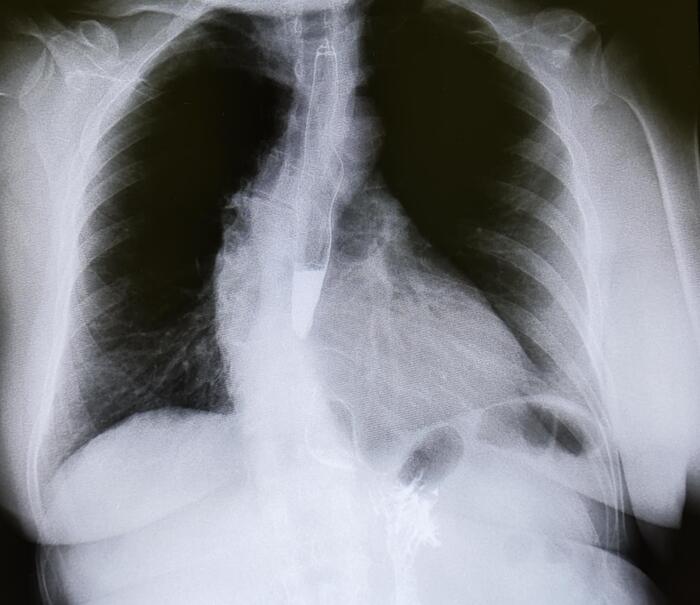

Эностоз может встречаться в любой кости, но чаще всего обнаруживается в губчатом веществе костей (например, в позвонках, тазовых костях, ребрах, длинных трубчатых костях).